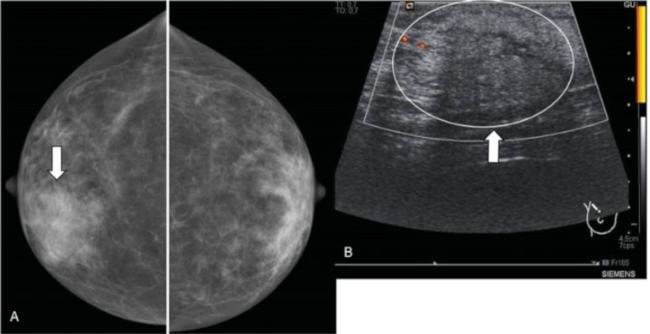

Neoplasia de origen fibroepitelial. Su origen está fuera de los ductos y lóbulos, en el tejido conectivo. Representa menos del 0,5% de los tumores de la mama. Se clasifican en benignos (58%), potencialmente malignos o borderline (12%) y malignos (30%). Su presentación más habitual es como un nódulo sólido, palpable, de crecimiento rápido (►Fig. 7). Ecográficamente muestran una morfología redondeada o lobulada. Suelen tener una ecoestructura heterogénea aunque son fundamentalmente hipoecoicos. Presentan bordes bien definidos y buena transmisión del sonido.

Tumor Phyllodes. Mujer de 45 años con antecedente de fibroadenoma en mama derecha que acudió por nódulo palpable de nueva aparición en mama izquierda. (A) Mamografía digital. Nódulos bilaterales, el de mayor tamaño en cuadrante superior externo (CSE) de mama izquierda (flecha amarilla). (B) Ecográficamente es un nódulo sólido, de bordes lobulados y ecogenicidad heterogénea (flecha), con zonas de buena transmisión del sonido. (c) RM con contraste iv. Nódulo hipervascular de bordes bien definidos (flecha). Tanto en la BAG como en la extirpación completa, el resultado histológico es de Tumor Phyllodes.